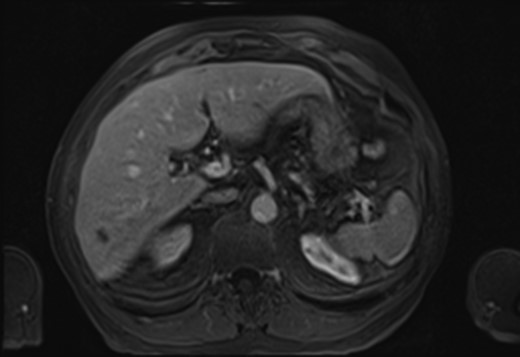

A 70-year-old gentleman with renal cell carcinoma resected by a robotic partial nephrectomy was found to have a single 10 mm lesion in segment 6 of his liver on a pre-operative staging computer tomography (CT) staging scan. Post-operative magnetic resonance imaging (MRI) confirmed low-signal intensity on pre-contrast T2-weighted images (T2-WI) which had grown slightly to s 11 mm. Following gadolinium, the lesion appeared hypovascular with no ring enhancement (Fig. 1). A contrast-enhanced ultrasound (CEUS) confirmed a hypovascular lesion in the arterial phase but had marked and progressive washout in the immediate and late phase. A PET scan showed some low grade fluorodeoxyglucose (FDG) uptake in the liver, and it was thought that the lesion may have been a primary hepatocellular carcinoma. The patient went for percutaneous biopsy and ablation of the lesion. Two core biopsies were taken and the histological appearance demonstrated a fibro-vascular lesion with numerous small, capillaries lined by atypical endothelial cells and surrounded by fibromyxoid stroma. Immunohistochemical staining had high expression of ERG, CD34, CD31 and factor XIIIa, confirming the endothelial nature and negative for Hep Par 1, CK7 and CK19. The appearances were consistent with an epithelioid haemangioendothelioma (Fig. 2). Post-procedure CT scan after 1 month showed adequate ablation margins with no new lesions.

MRI Scan showing hepatic epithelioid hemangioendothelioma (HEHE).